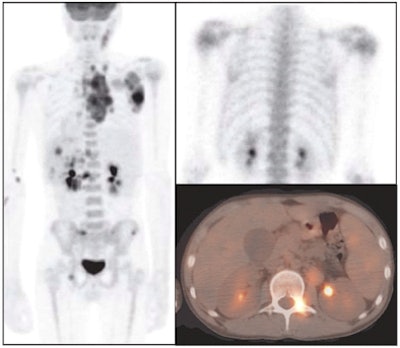

| Images of a 23-year-old man with relapsed nodular sclerosing Hodgkin's lymphoma; FDG-PET shows a greater extent of disease involvement. The top images show anterior (left) and posterior (right) spot views of bone scan, which indicate mildly increased uptake in the left acetabulum and right inferior pubic ramus. The bottom panel illustrates FDG-PET posterior maximal intensity projection (left), coronal fusion (center), and transverse fusion (right) images, with many focal areas of abnormal uptake in the pelvis and proximal femurs. |